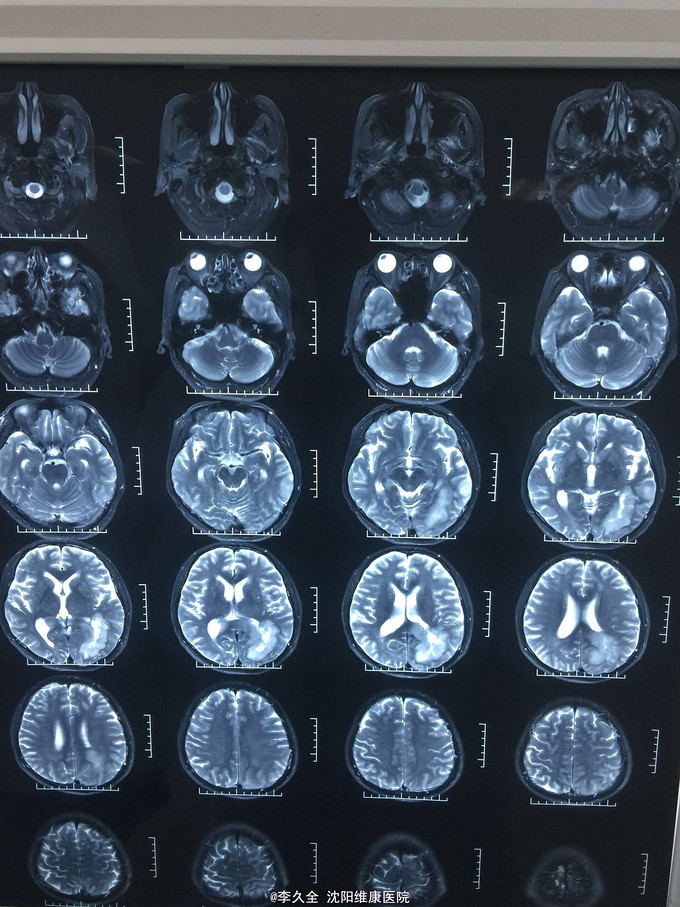

男,62岁,以头晕、视野缺损、记忆力减退、失写、失算7个月入院! 现病史:去年7月出现头晕,就诊于医院,行头CT:代诉未见异常,口服药物无效,后出现右侧视野缺损,走路撞墙、撞门,就诊于当地医院、北京协和医院,考虑“㬵质瘤”,近3个月出现近事遗忘为主,平时写字不会,计算力下降,不认识人! 既往史:2型糖尿病5年!

查体:BP:150/80mmHg,心肺腹无异常。神清,不能言语,失写、失算、失认,双曈孔等大正圆,直径3.0mm,光敏,四肢能够活动,右侧肌张力增高,巴氏征R+L-,颈强3横指,克氏征阳性! 影像MR:

1.颅内占位,胶母可能大! 2.2型糖尿病